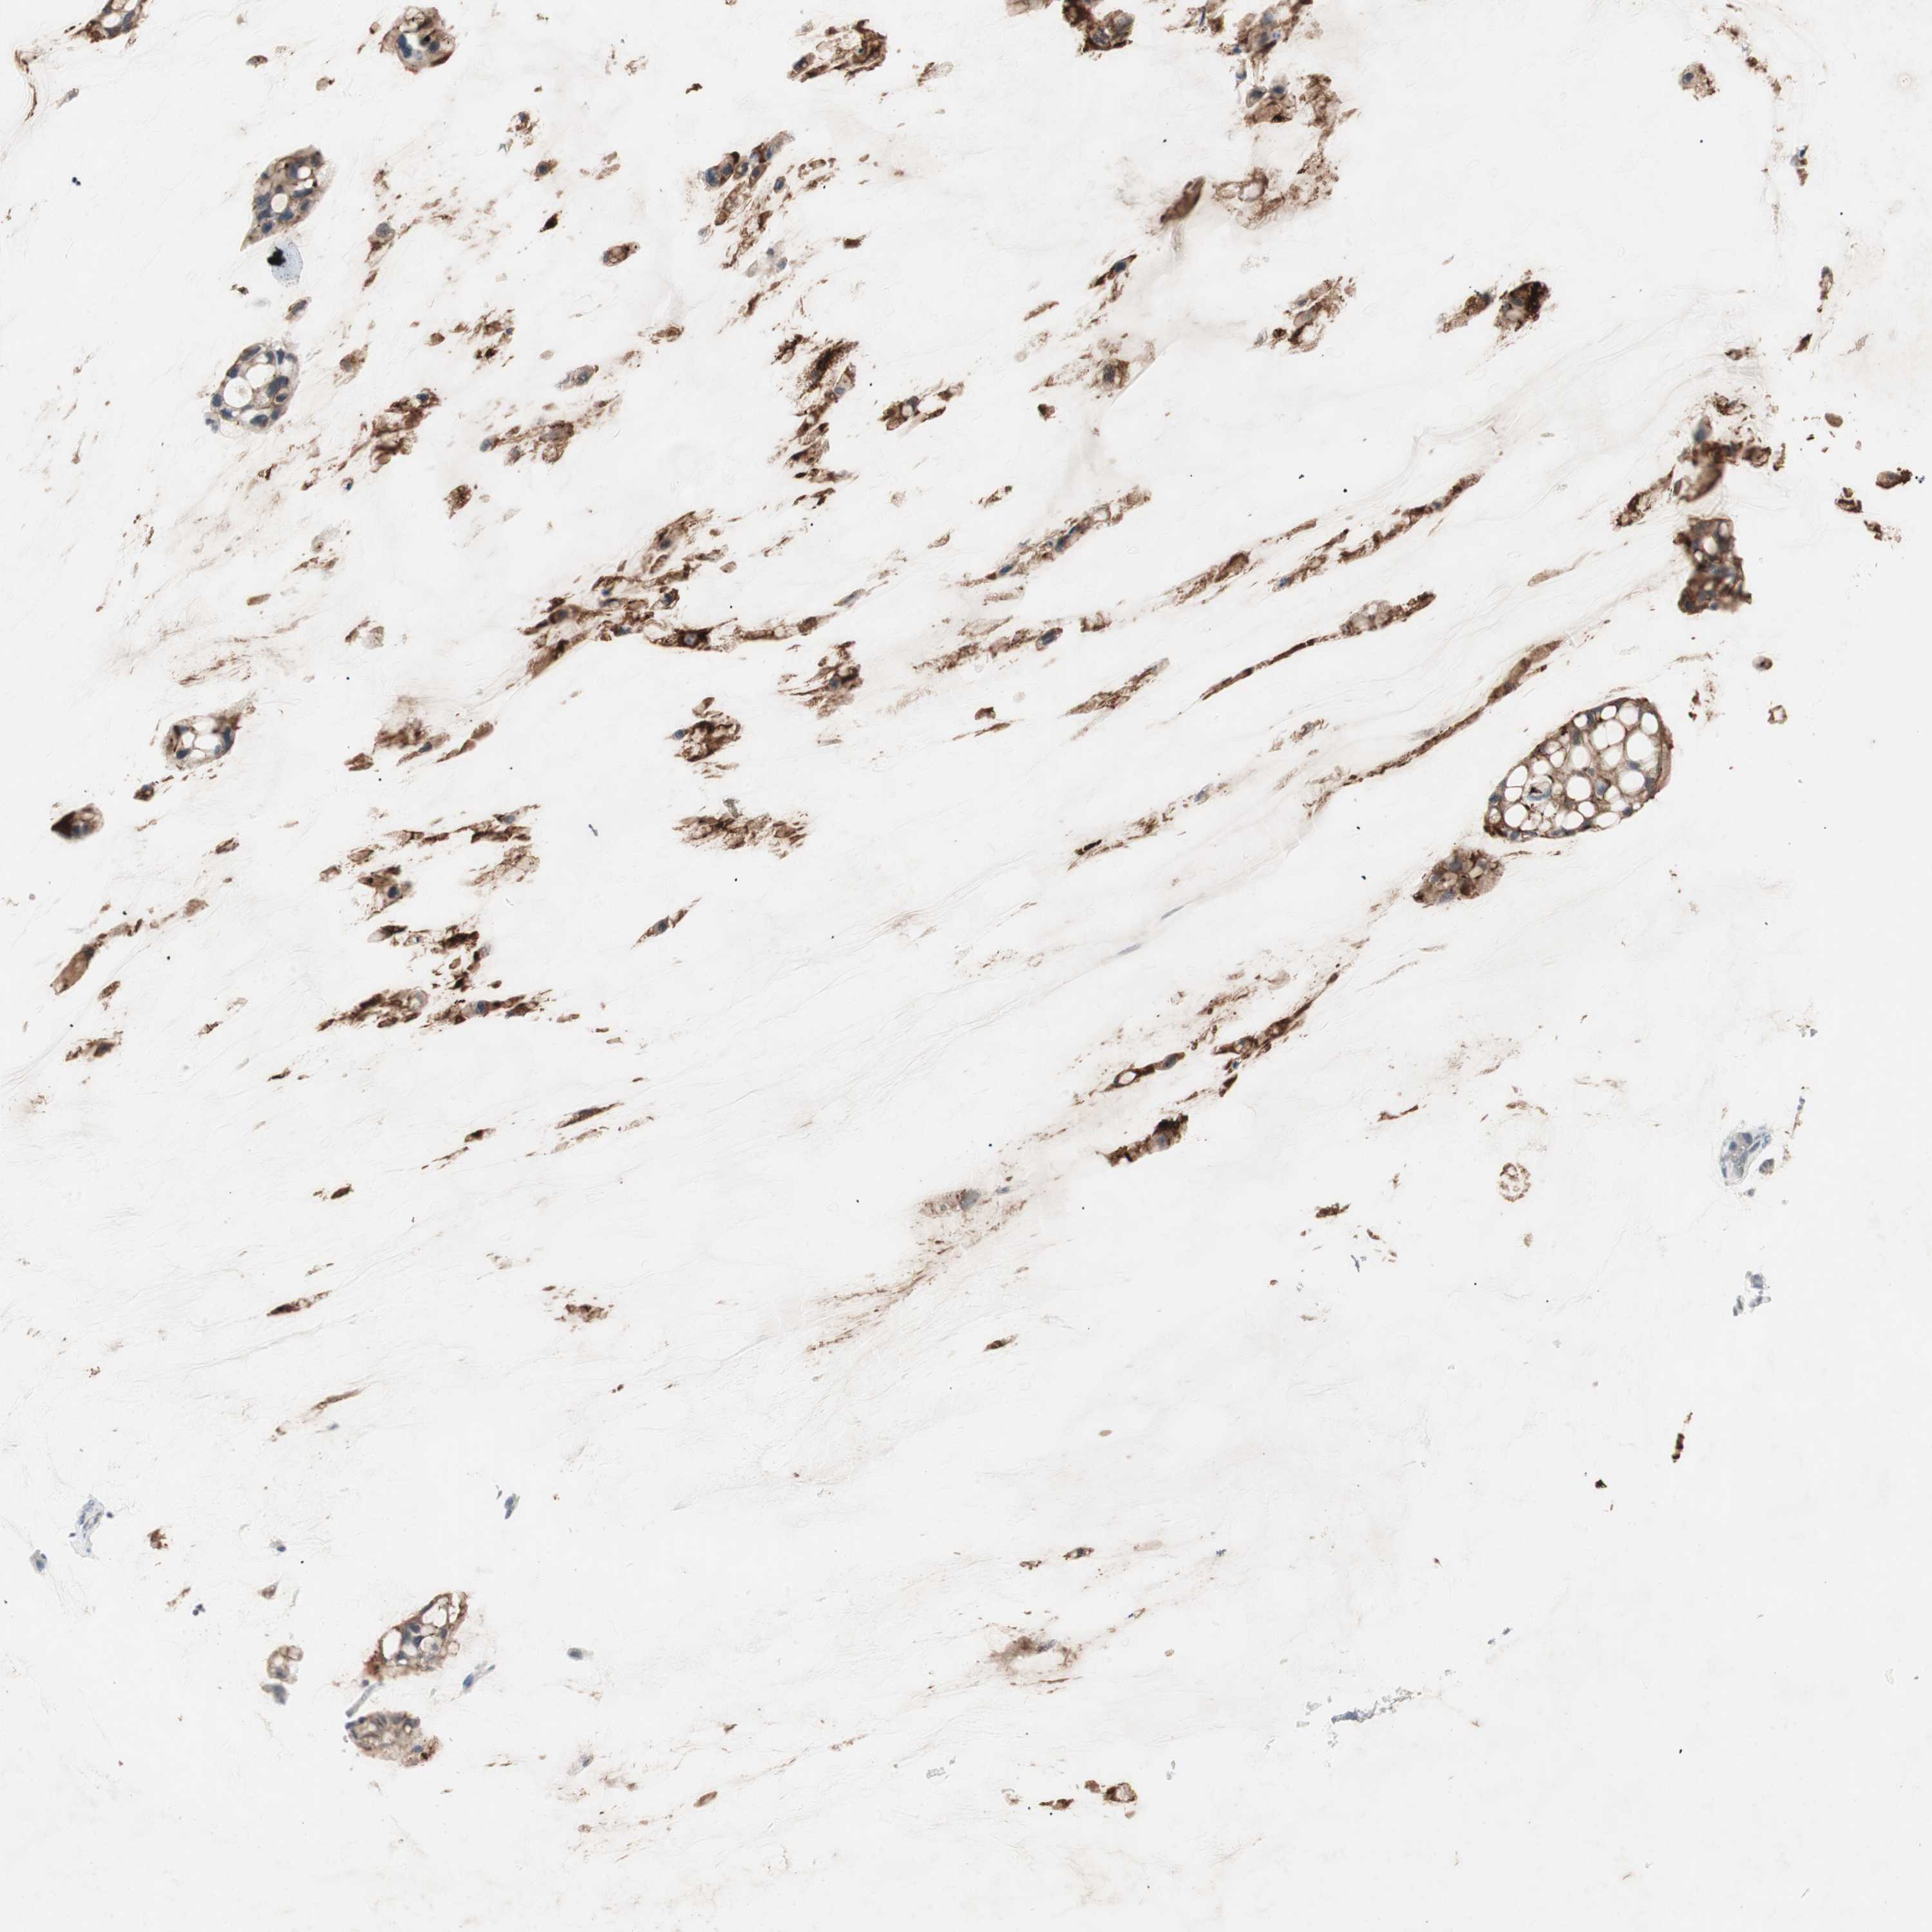

OVARIAN CANCER - Protein expressioni

A mouse-over function shows sample information and annotation data. Click on an image to view it in a full screen mode. Samples can be filtered based on level of antibody staining by selecting one or several of the following categories: high, medium, low and not detected. The assay and annotation is described here.

Note that samples used for immunohistochemistry by the Human Protein Atlas do not correspond to samples in the TCGA dataset.

Antibody stainingi

Antibody staining in the annotated cell types in the current human tissue is reported as not detected, low, medium, or high, based on conventional immunohistochemistry profiling in selected tissues. This score is based on the combination of the staining intensity and fraction of stained cells.

Each image is clickable and will lead to virtual microscopy that enables deeper exploration of all samples and also displays staining intensity scores, fraction scores and subcellular localization as well as patient and tissue information for each sample.

Antibody HPA036348

Antibody HPA036349

Antibody CAB002422

Antibody CAB005258

Cystadenocarcinoma, serous, NOS

Carcinoma, NOS

Cystadenocarcinoma, mucinous, NOS

Carcinoma, endometroid